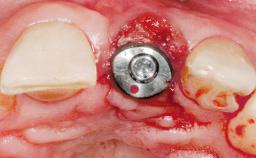

Late Placement of an Implant in a Maxillary Left Central Incisor Site

Bone Augmentation Horizontal|Staged

Augmentation Materials Xenogenous|Membrane

Soft Tissue Grafting Simultaneous

Bone Volume Deficient horizontally, requiring prior grafting